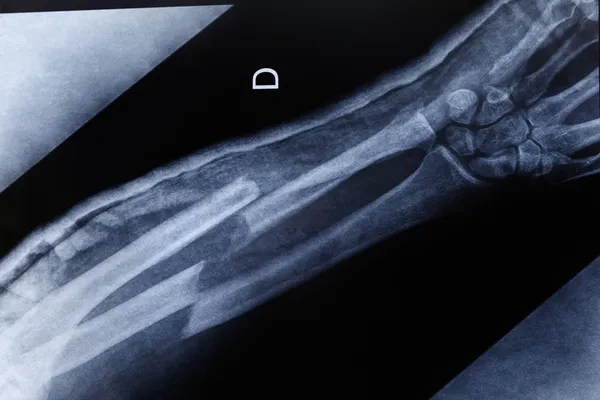

EN SIK KALÇA VE EL BİLEĞİNDE GÖRÜLÜYOR

Osteoporoza bağlı kırıkların hafif bir travmayla veya kendiliğinden de gelişebildiğine dikkat çeken Uzm. Dr. Kirez, "En sık omurga, kalça ve el bileğinde kırıklar oluşmaktadır. Kırıklar gelişmeden osteoporozun farkına varmak ve tanı koymak açısından taramalar önem arz etmektedir" dedi.